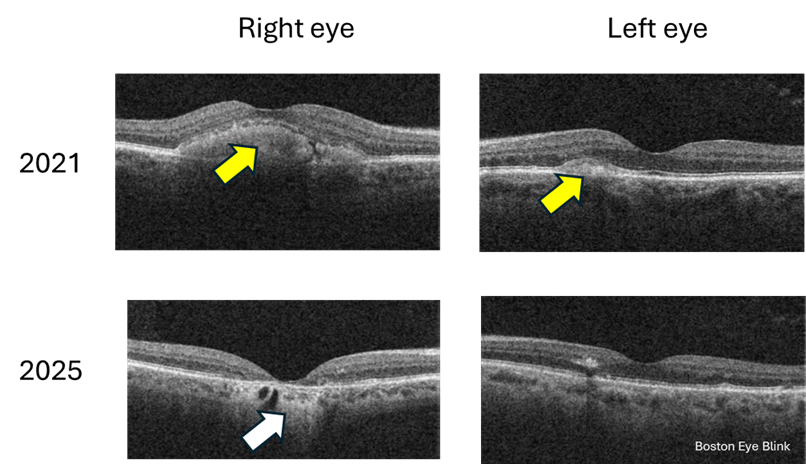

Then came the man in his sixties a week later. The two patients are not related. Just a coincidence that I would see two cases of a rare eye condition in the span of a week in a primary care setting. He started noticing blurry vision in the right eye when he was 50. He came to see us in 2021 but then lost to follow up. It gradually got worse, and now his right eye sees 20/40. His left eye sees 20/20 and no change over the years. Again, imaging confirmed the diagnosis. What is interesting is that you can see that over the 4 years, the right eye has progressed from the ‘egg yolk’ stage to ‘atrophy’ stage; while the left eye has little progression with still early or small ‘egg yolk’.

Figure 2. Cross-section macular photo of a 60 year old man in 2021 and 2025. Yellow arrow points to the ‘egg yolk’; white arrow points to atrophied retina.